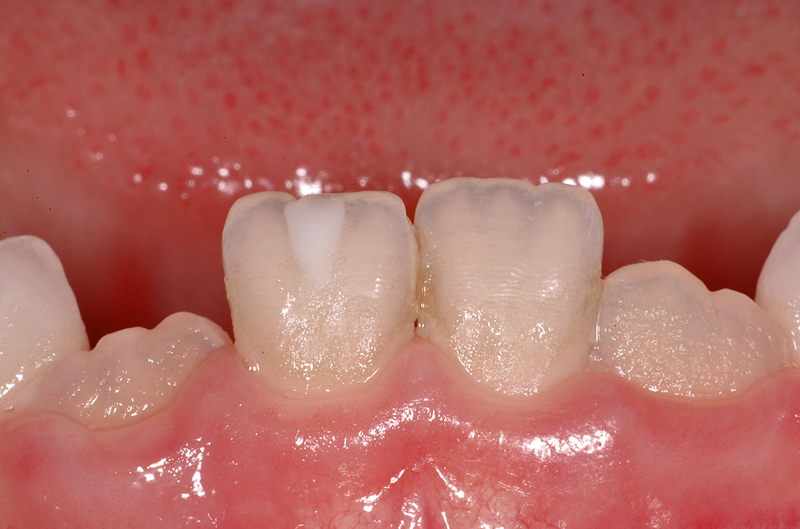

Hier ein weiterer Fall mit einem dreieckigen, weissen opaken Fleck an einem unteren, mittleren rechten Schneidezahn (Zahn 41). Bei diesem Fall ist der Unterschied zum natürlichen «Farbenspiel» des Zahnes auf der linken Seite gut zu sehen. Auch diese weisse Opazität braucht keine Therapie und kann belassen werden.

In den Zahnzwischenräumen sind bräunliche Verfärbungen auf Grund einer nicht ganz optimalen Mundhygiene zu sehen, auch ist gegen den Zahnfleischrand hin ein matter Zahnbelag (bakterielle Plaque) zu sehen. Beides kann mit einer Bürste entfernt werden.

- Dreieckiger, weisser Fleck an 41